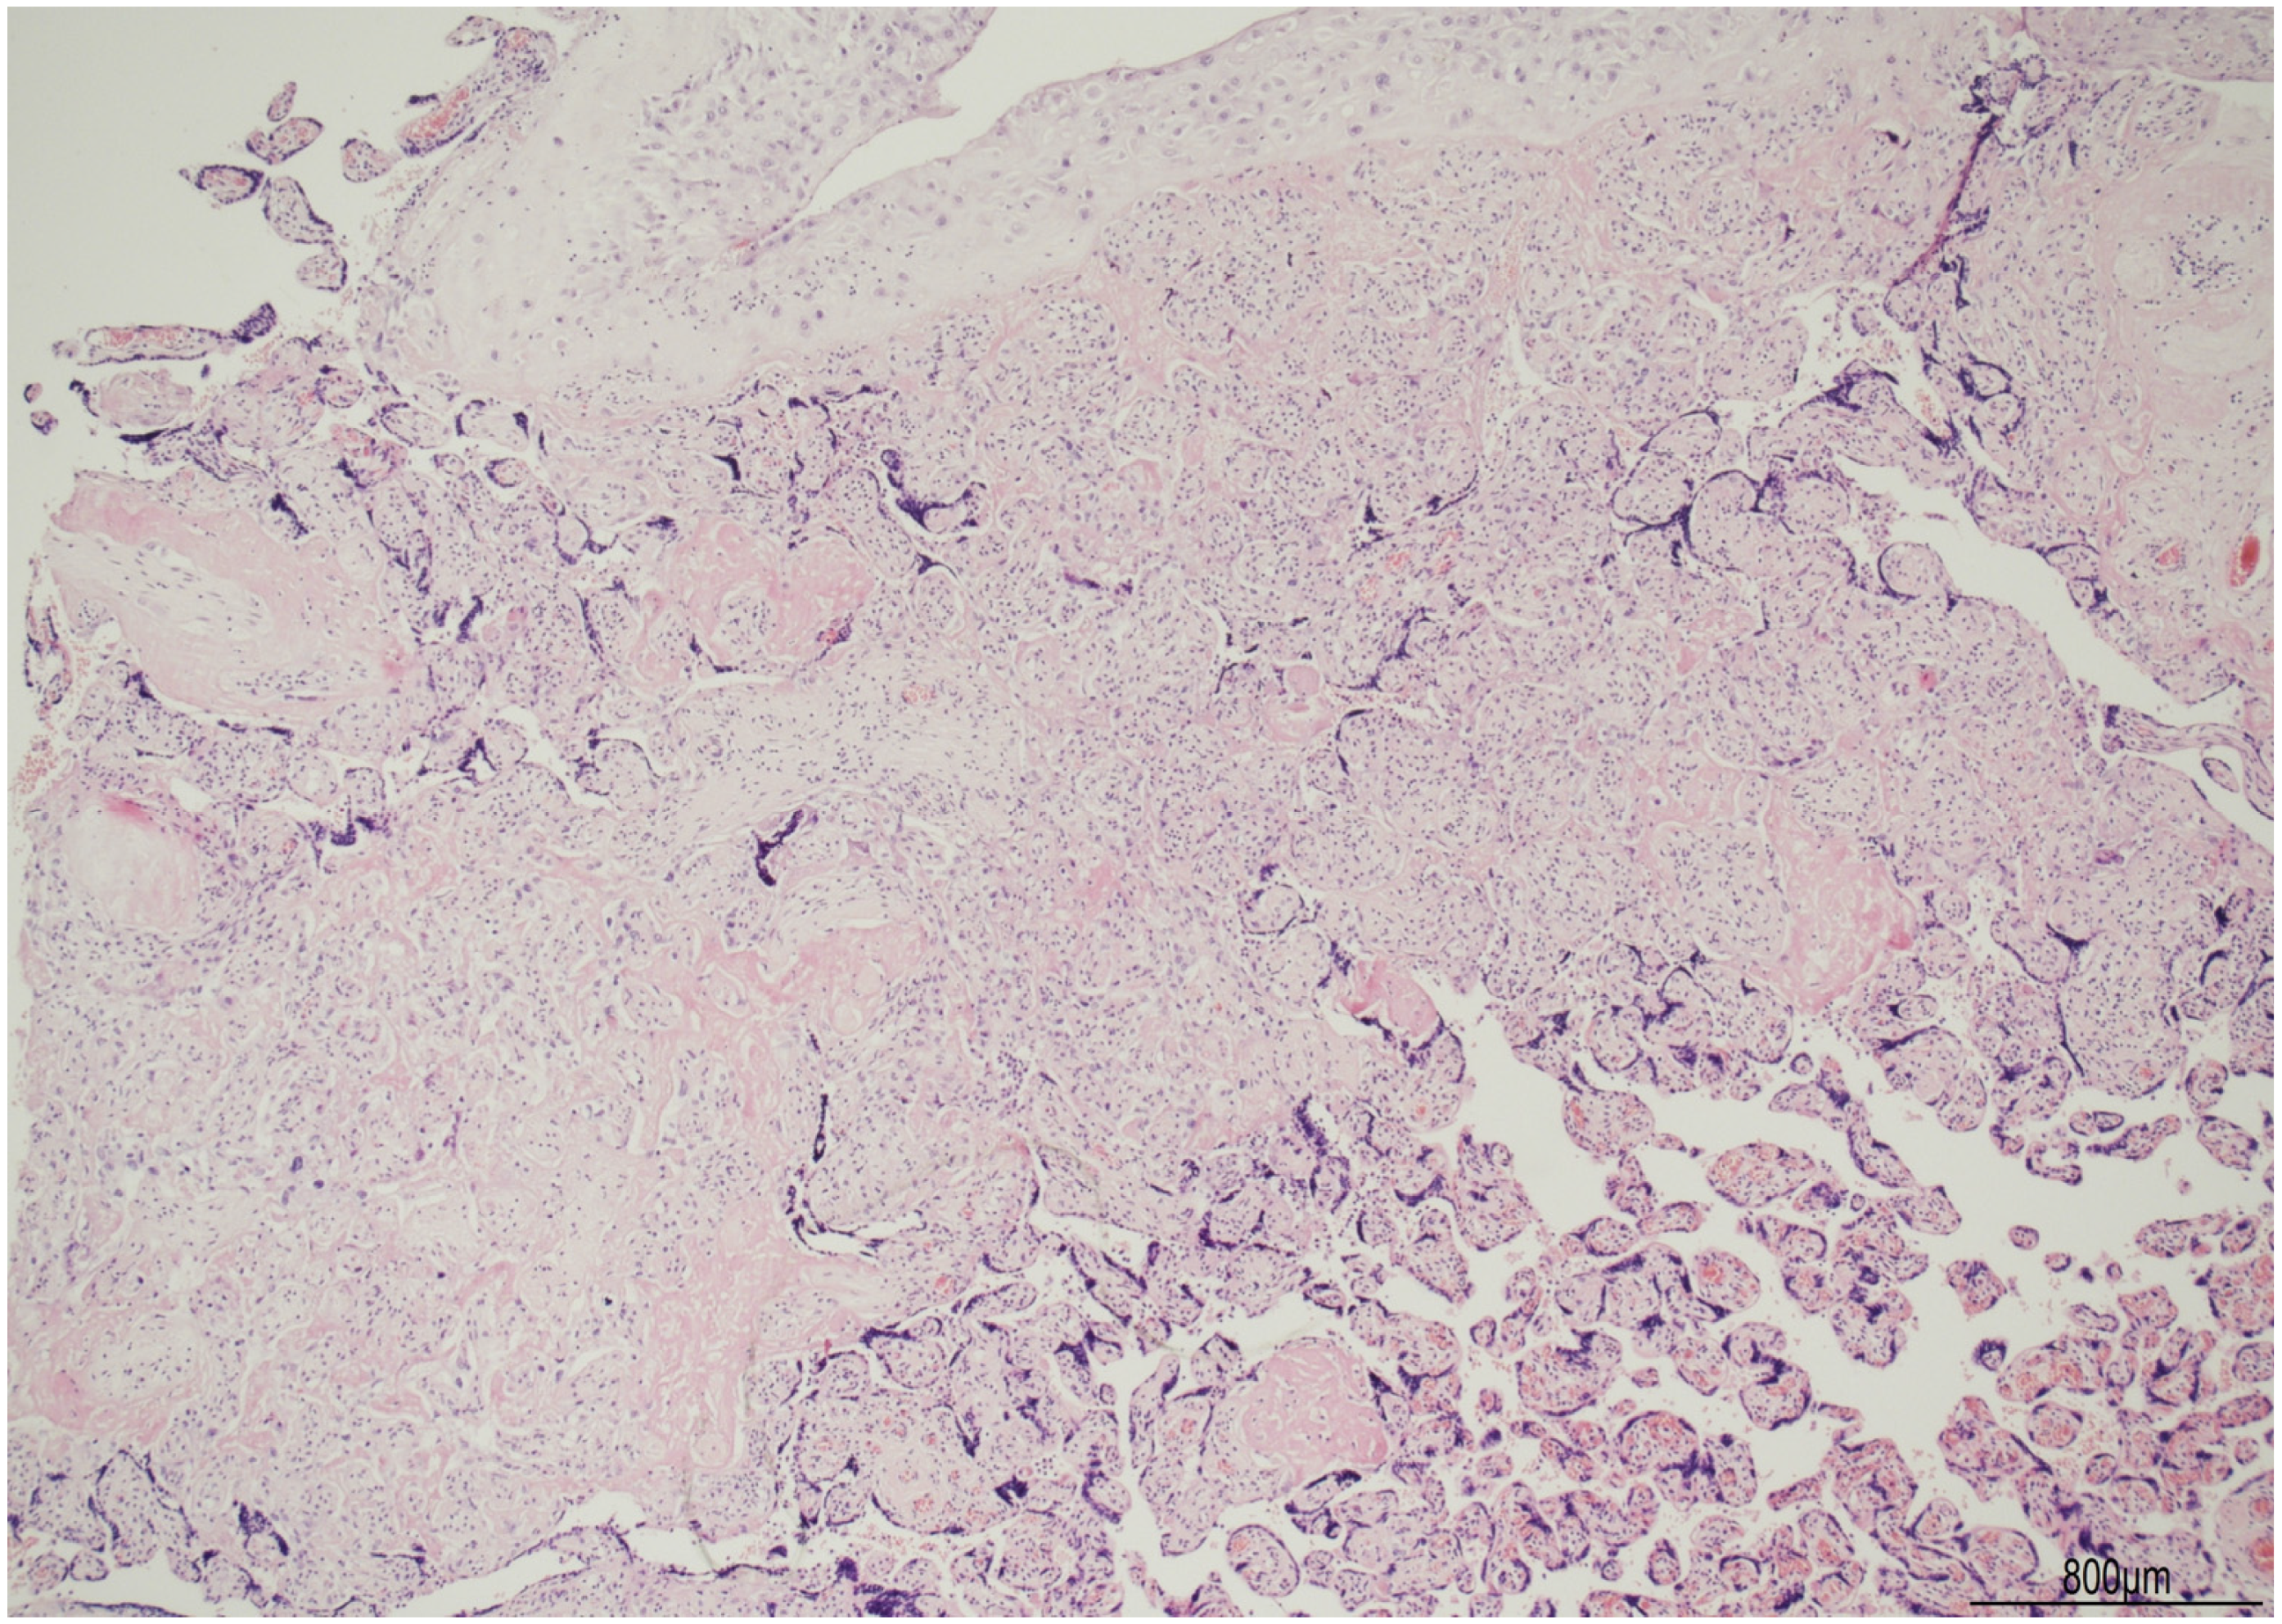

Discordant Eosinophilic/T-Cell Chorionic Vasculitis in a Dichorionic Diamniotic Placenta

2. Case Description